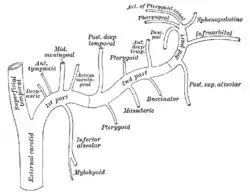

Plan of branches of internal maxillary artery. (Label "Deep auric." visible at upper left.) | |

Plan of branches of internal maxillary artery. (Deep auricular visible but not labeled.) | |